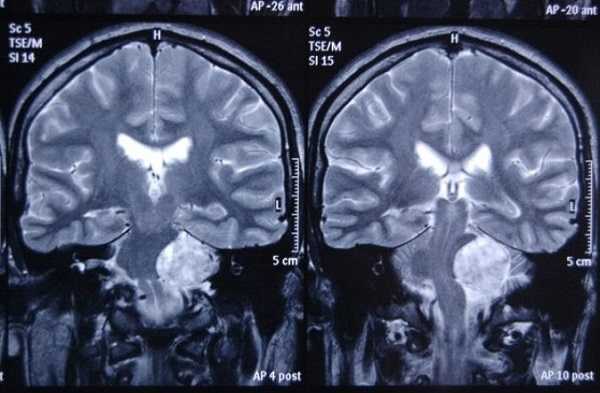

МРТ головного мозга. Корональная Т1-зависимая МРТ. Липома мосто-мозжечкового угла.

Липома представляет собой жировые клетки под паутинной оболочкой мозга. Липомы формируются в период эмриогенеза в связи с неправильным расположением зачаточных жировых клеток в области мозговых оболочек. остатков примитивной эмбриональной оболочки. Липома может рассматриваться как аномалия развития и как доброкачественные опухоли из группы мезенхимальных опухолей (оболочечные неменинготелиальные). Частота липом составляет не более 1% от кистоподобных образований и еще меньше от опухолей мозга. Липомы чаще всего располагаются по средней линии: в межполушарной щели, в мозолистом теле, воронке гипофиза и гипоталамусе , реже вокруг червя мозжечка и пластины четверохолмия. Однако встречаются внеосевые липомы, например, в мосто-мозжечковом углу. Липомы головного мозга, в отличие от позвоночника, изредка сочетаются с другими аномалиями развития. Липома мозолистого тела часто видна в месте с недоразвитием его задней трети и изредка с переходом жировой ткани на сосудистое сплетение желудочков. При МРТ головного мозга имеет типичные черты: она может иметь любую форму, но резко очерчена, без перифокального отека и не дает масс-эффекта, не разрушает соседние структуры. Внутри липома чаще изредка неоднородная из-за участков кальция и сосудов. Главный признак липомы - она имеет интенсивности сигнала жировой ткани при МРТ, то есть выраженно гиперинтенсивная на Т1-зависимых МРТ головного мозга и немного менее интенсивная по отношению к ликвору на Т2-зависимых МРТ головного мозга. В отличие от близких по виду эпидермоидных и тератоидных кист, МРТ головного мозга с подавлением жира показывает полное исчезновение жирового сигнала.

При МРТ в СПб мы не видим сложности в диагностике липом ни в высоких полях, ни в низких открытых МРТ, однако, выявление при МРТ головного мозга такой ее локализации как мосто-мозжечковый угол требуют внимания ввиду того, что здесь встречаются другие сходные образования (эпидермоиды, опухоли). Об МРТ головного мозга при других кистах можно читать в специальной статье.